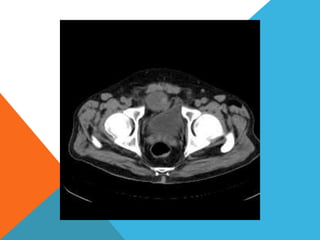

El paciente presentó síntomas de sangrado digestivo y pérdida de peso. Exámenes revelaron gastritis crónica asociada a H. pylori. Un tumor fue descubierto en una colonoscopia normal. La cirugía removió un tumor fibroide solitario, una rara neoplasia mesenquimal que usualmente crece lento y tiene bajo potencial de malignidad. El pronóstico después de la remoción quirúrgica es generalmente bueno.